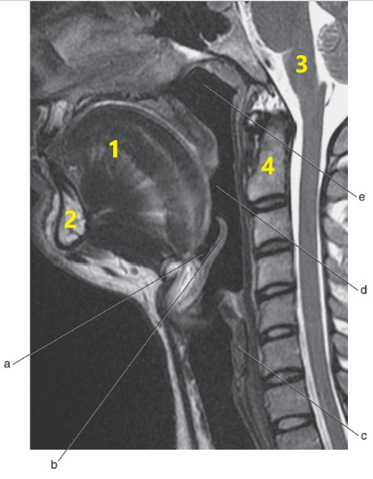

What is # 1 ?

Mandible

What is # 4 ?

C-1/C-2

Tongue

What is # 3 ?

Brain stem